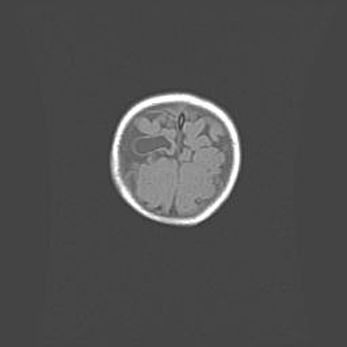

Наружная гидроцефалия с возможной атрофией височных областей.

Возраст: 28 дней

Вес: 3670 г

Пол: мужской

Окружность головы: 38 см

Срок гестации: 40 недель

Гидроцефалия головного мозга у новорожденных – это заболевание, которое характеризуется скоплением избыточного количества спинномозговой жидкости в желудочковой системе головного мозга в результате затруднения её перемещения от места выработки к месту поглощения в кровеносную систему или вследствие нарушения абсорбции. При открытой наружной форме гидроцефалии у новорожденных расширяются и переполняются субарахноидные пространства.

При нормотензивных  формах,  которые,  как  правило,  являются  следствием  перенесенных ишемических  повреждений  паренхимы  мозга,  возможно  сочетание микроцефалии  с нормотензивной гидроцефалией. В основе данных изменений лежит атрофия больших полушарий с преимущественной  локализацией  в  лобно-височных  областях.